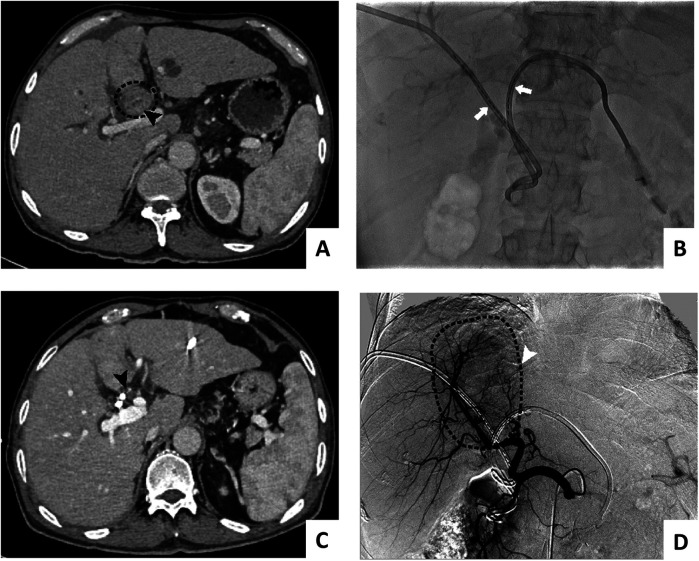

Abstract Image